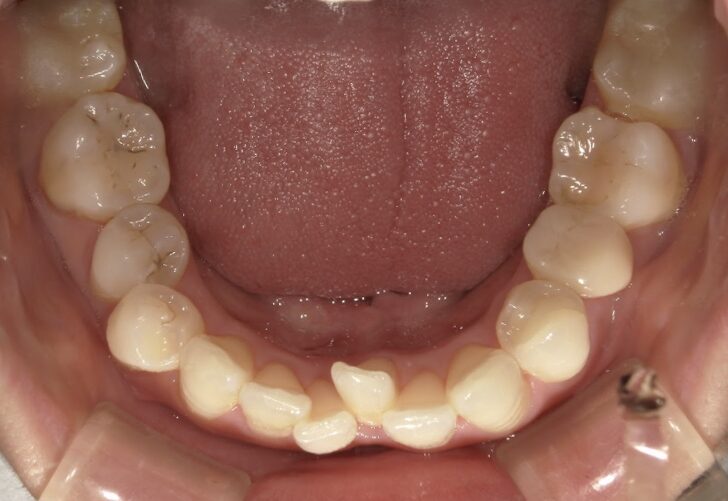

治療前

前歯が全く当たっていないを主訴に当院を受診され、開咬・上顎前突・下顎叢生を認めました。

上顎左右4番抜歯を行いIPRを使用してマウスピース型矯正装置(インビザライン)を使用し、改善を行いました。

抜歯部位上顎左右4番